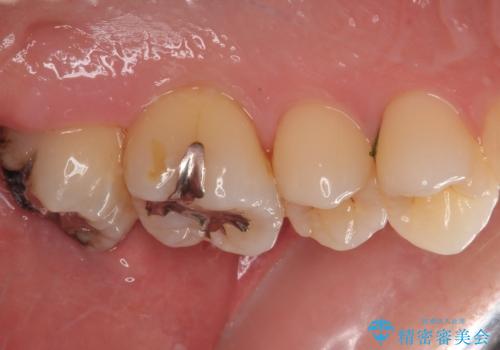

- 元々むし歯があったものの、処置が困難とのことでしたが、矯正治療を終えたので処置をしたいとのことで来院された患者様です。

左右ともに最後臼歯が頬側に顕著に突出しており、むし歯になってしまったことが想像されました。

矯正治療により処置が可能な位置に歯が移動したため、オールセラミッククラウンにて補綴治療を行うこととしました。